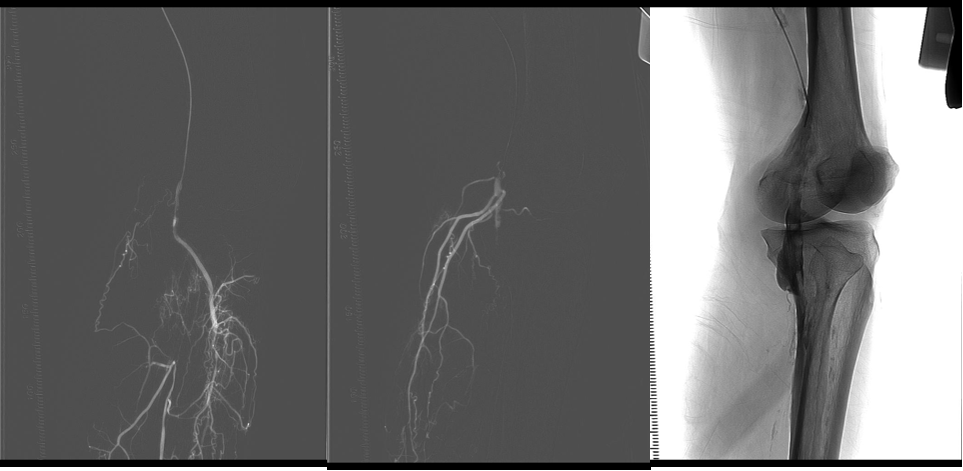

★ 病例介绍

男,81岁;

左足第4、5足趾溃疡2+周

既往:糖尿病病史30年;

ABI:L:0.57;R:0.19

★ 手术过程

图:术中

★ 手术结果

图:手术结果